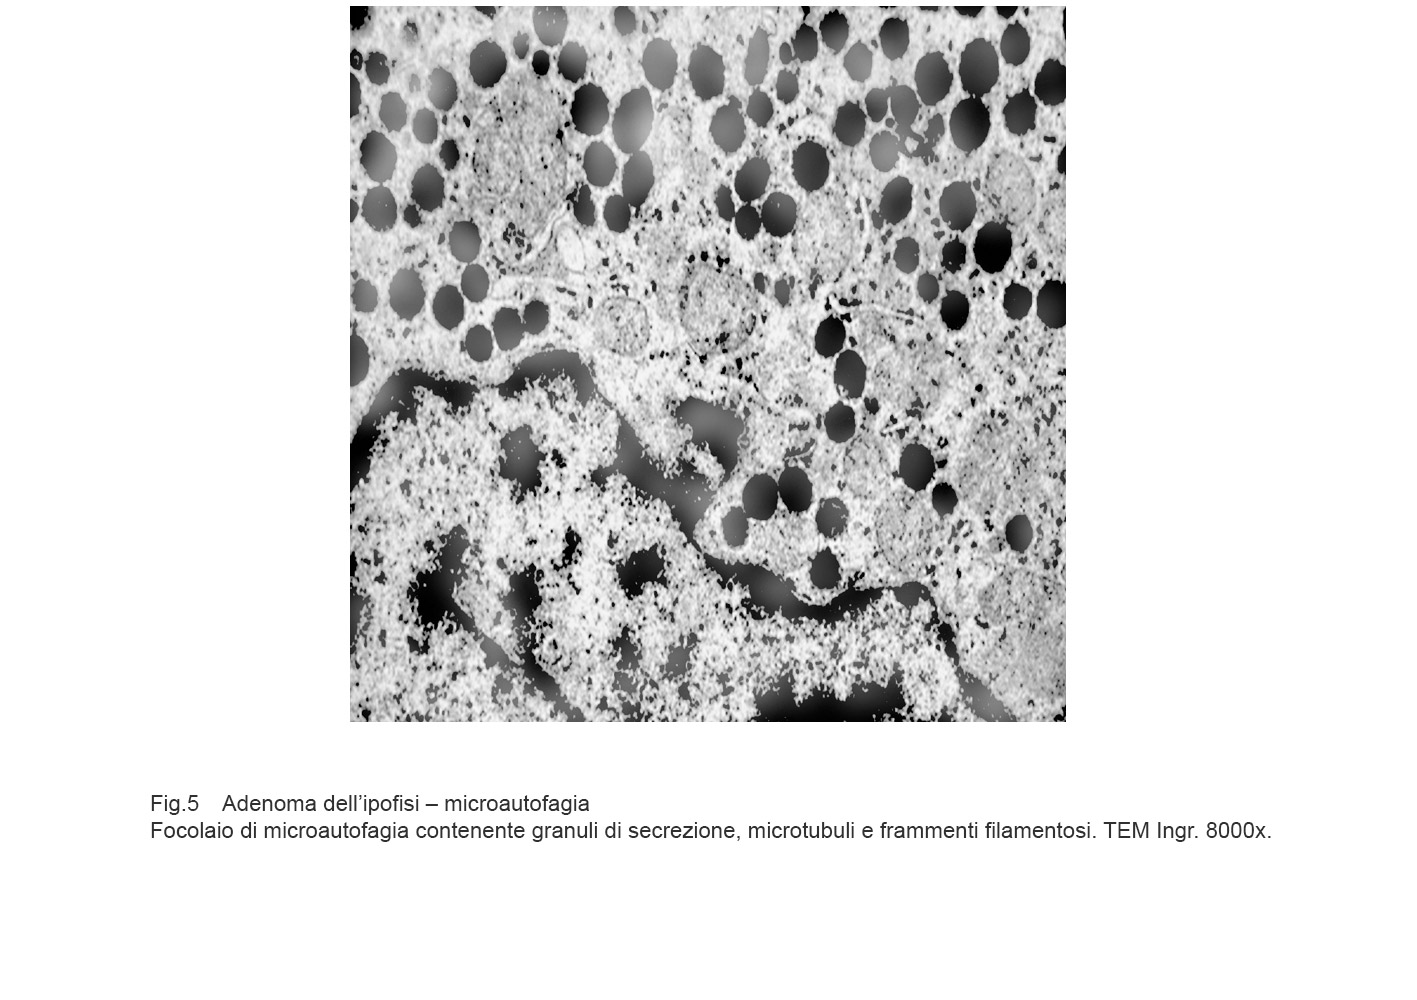

MICROAUTOFAGIA

I focolai di microautofagia si ritrovano frequentemente commisti a mitocondri disfunzionali e a reticolo- endoplasmatico in stato di stress.

Essi sono di piccole dimensioni, appaiono come vescicole, delimitate da una membrana a doppio strato, immerse nel citosol e

ricolme di materiale amorfo oppure di materiale amorfo commisto a frammenti filamentosi.

Fig.5  Fig.5a

Fig.5a